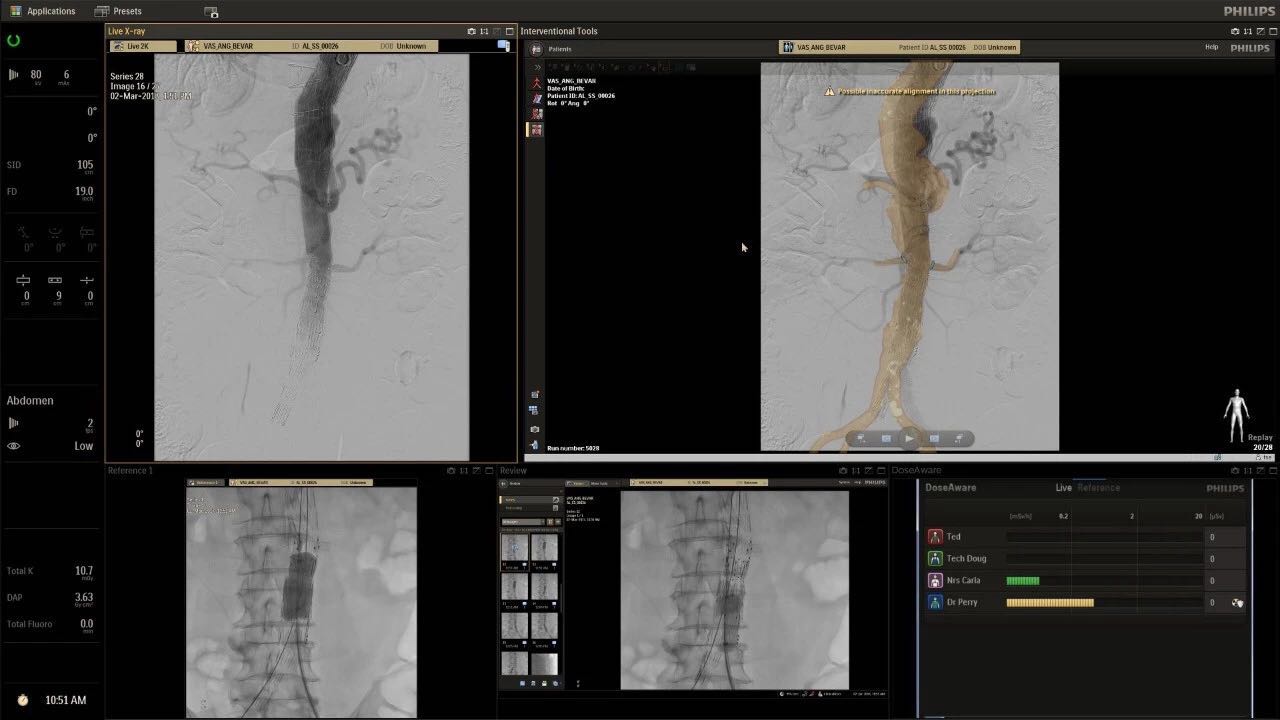

在日益復(fù)雜的干預(yù)期間,臨床醫(yī)生需要快速、輕松地可視化關(guān)鍵解剖結(jié)構(gòu)并確定手術(shù)過(guò)程中患者的變化。2019年1月17日,飛利浦宣布推出采用FlexArm的Azurion 7 C20,旨在提高圖像引導(dǎo)程序的定位靈活性。

帶有FlexArm的Azurion 7 C20 包含一系列創(chuàng)新技術(shù),使臨床醫(yī)生可以更輕松地在整個(gè)患者身上進(jìn)行二維和三維成像。當(dāng)臨床醫(yī)生移動(dòng)系統(tǒng)時(shí),圖像光束自動(dòng)保持與患者的對(duì)準(zhǔn),允許更一致的可視化并使他們能夠?qū)⒆⒁饬性谥委熒稀?/span>

飛利浦表示,采用FlexArm設(shè)計(jì)的Azurion 7 C20可提供卓越的靈活性和直觀的控制。該系統(tǒng)由智能運(yùn)動(dòng)引擎驅(qū)動(dòng),可在八個(gè)不同的軸上移動(dòng),所有這些軸均由其單個(gè)“Axsys”控制器控制。臨床醫(yī)生的模擬測(cè)試表明,該系統(tǒng)有可能顯著減少患者,工作人員和設(shè)備的重新定位,從而改善微創(chuàng)手術(shù)的可及性,包括通過(guò)患者手腕進(jìn)入身體的手術(shù)(橈動(dòng)脈入路),并降低患者的風(fēng)險(xiǎn)。無(wú)意中拔出電線和管子,以及節(jié)省大量時(shí)間。該系統(tǒng)非常適合混合手術(shù)室(OR),可滿足一個(gè)房間內(nèi)的多種專業(yè)需求,例如手術(shù)和血管內(nèi)手術(shù)的組合。

FlexArm在不少于8軸的情況下旋轉(zhuǎn),從而創(chuàng)建幾乎無(wú)限的靈活性來(lái)執(zhí)行成像,從頭部到腳部在左側(cè)和右側(cè)進(jìn)行2D和3D可視化。圖像光束保持與患者對(duì)齊,允許在旋轉(zhuǎn)或角度期間更好地可視化解剖結(jié)構(gòu)。使用Axsys運(yùn)動(dòng)控制系統(tǒng)輕松操作支架。